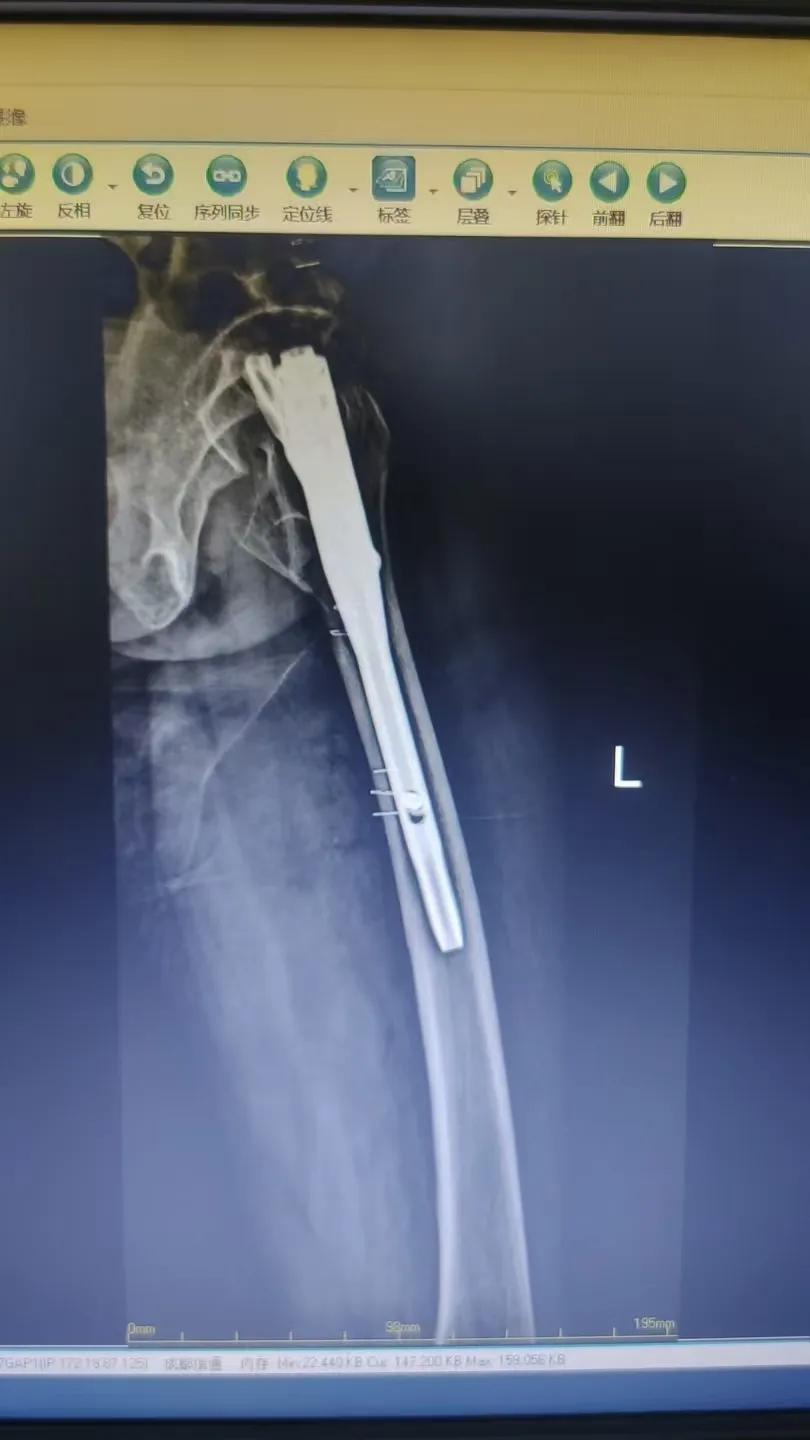

PFNA術(shù)式屬于髓內(nèi)固定系統(tǒng),具有創(chuàng)傷小、固定牢、出血少、愈合快的優(yōu)點(diǎn),尤其適用于高齡轉(zhuǎn)子間骨折患者,是提升手術(shù)安全性與效果的關(guān)鍵技術(shù)。

手術(shù)在麻醉科的保駕護(hù)航下順利完成。術(shù)中采用微創(chuàng)小切口,精準(zhǔn)置入PFNA髓內(nèi)釘。

術(shù)后復(fù)查顯示骨折對(duì)位對(duì)線良好,患者疼痛顯著緩解,在醫(yī)護(hù)人員指導(dǎo)下逐步開始康復(fù)鍛煉,重燃站立行走的希望。